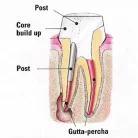

Cylindro-conical design:

- 2/3 parallel – excellent retention

- 1/3 conical to correspond to the shape of the root canal

- Prepare the post space using specific drills

- Trial fit the Fiber posts and determine the desired length.

- After etching and rinsing the canal and super-structure, place the adhesive on the tooth.

- Place the dual cure resin cement and core build-up material.

- Final preparations. Note that the posts has to be placed over the centric cusps.